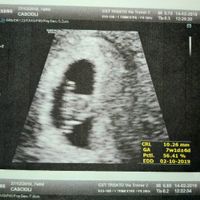

Prima ecografia e allarmismo dei medici

Alessandra in Future mamme, Il 14 Febbraio 2019 alle 15:50

Oggi sono a 7+0 considerando l'ultimo ciclo e ho fatto la prima ecografia privatamente per vedere se c'era il battito. Su questa ecografia a me neanche sembra un embrione, è parecchio strano 😏 alla...

Alessandra, giovedì 14-Feb-19 28 1.450